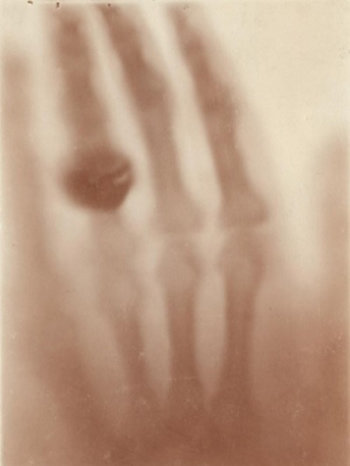

부인 베르타 뢴트겐의 손을 X-ray로 촬영한 이미지

빌헬름 뢴트겐은 수학에서 ‘미지의 속성’을 가리키는 ‘X’를 붙여 이 광선의 이름을 ‘X-ray’라 명명했다. 이렇게 미지의 광선인 X-ray가 탄생한 것이다. 첫 발견 이후 두문불출하며 7주간의 밤낮없는 연구를 지속한 뒤 그는 논문을 발표해 세상에 ‘X-ray’를 소개하였는데, 이를 증명하기 위해 결혼반지를 낀 부인의 손을 X-ray로 촬영한 사진은 세계에서 가장 유명한 사진 중 하나로 남게 되었다.